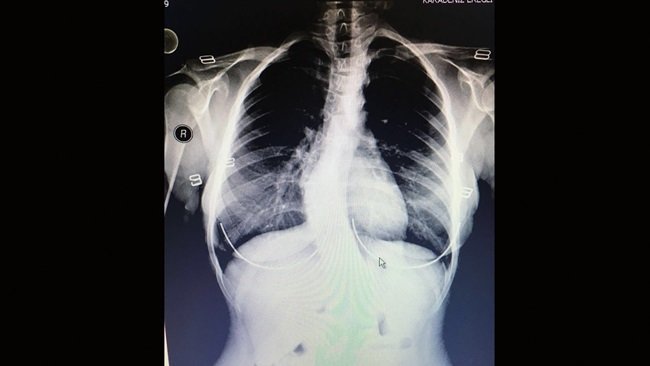

Kdz. Ereğli ilçesinde yaşayan 17 yaşındaki Gaye Güntay’, vücudundaki eğrilik ve sırt ağrıları sonrasında 2015 yılında Devlet Hastanesi’ne gelerek Beyin Cerrahı Uzmanı Opr. Dr. Mustafa Kaya tarafından muayene ve tetkikleri yaptırdı. Genç kıza, skolyoz hastalığı teşhisi konuldu. Hastanede çekilen filmlerinde sırt omurgasının omuzdan kuyruk sokumuna kadar ‘S’ şeklinde olduğu tespit edilen Gaye Güntay’ın ameliyat olmasına karar verildi. 15 Mayıs 2016 tarihinde Opr. Dr. Mustafa Kaya tarafından başarılı bir ameliyat ile omurgası düzleştirilen Gaye Güntay, bir hafta süren tedavisinin ardından taburcu edilerek sağlığına kavuştu.

17 YAŞINDAKİ GAYE GÜNTAY'IN OMURGASINDAKİ EĞRİLİK KDZ. EREĞLİ DEVLET HASTANESİNDE GERÇEKLEŞTİRİLEN AMELİYAT İLE DÜZLEŞTİRİLDİ. (VEDAT KILIÇ/ZONGULDAK-İHA)

17 YAŞINDAKİ GAYE GÜNTAY’IN OMURGASINDAKİ EĞRİLİK KDZ. EREĞLİ DEVLET HASTANESİNDE GERÇEKLEŞTİRİLEN AMELİYAT İLE DÜZLEŞTİRİLDİ.